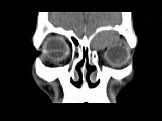

- 单项选择题男,53岁, 左眼痛、突出3年,结合图像, 最可能的诊断是 ( )

A、淋巴瘤

B、骨膜下脓肿

C、黏液囊肿

D、眼型Graves病

E、良性混合瘤